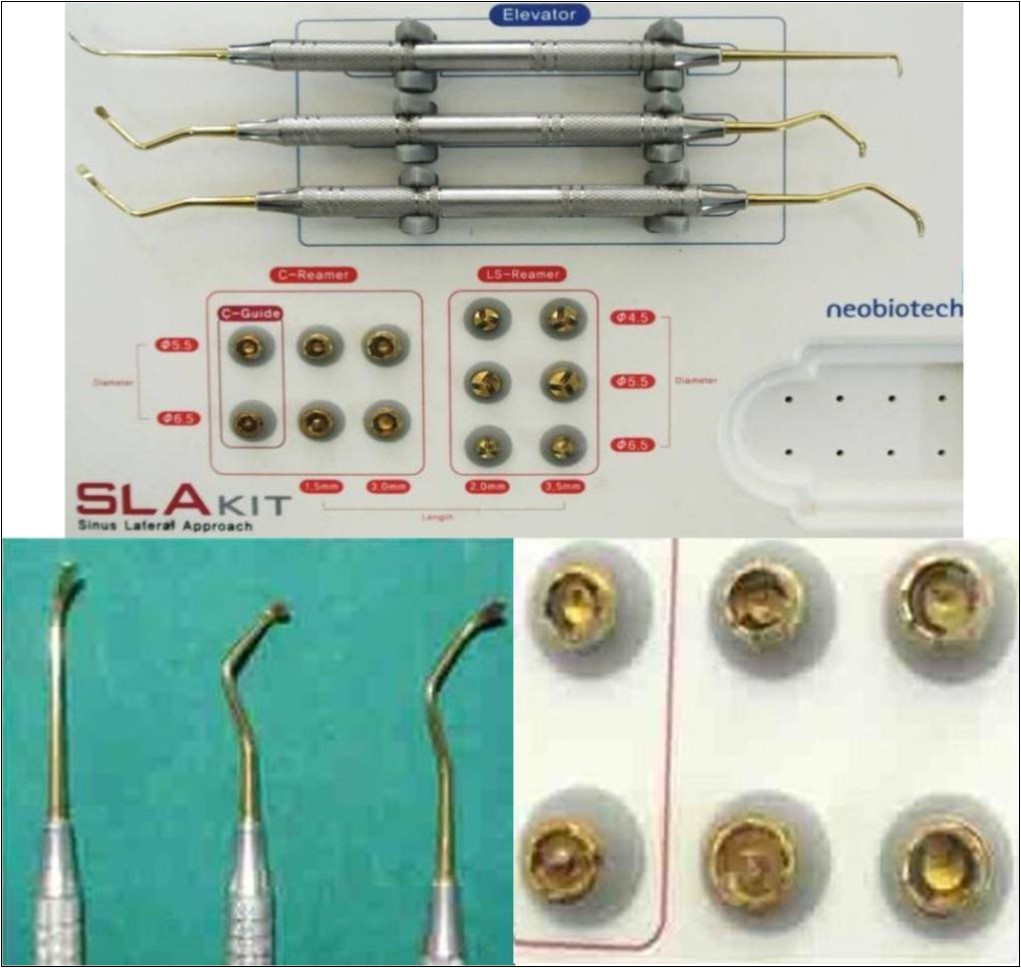

A total of 20 sinus augmentations were carried-out in 17 patients satisfying the criteria (inclusion and exclusion) requiring placement of implants in atrophic maxilla and in other situations of anatomic constraints. The patients were informed about the study including the use of the synthetic graft material and their approval was sought before their inclusion into the study. A written consent was obtained from each of the participating patient. After a detailed history and a thorough clinical examination, including systemic and regional/local examination, patients were taken-up for the sinus augmentation. The type of sinus augmentation procedure, direct or indirect, was decided based on the pre-operative residual bone height evaluated radiographically. The residual bone height was recorded using CBCT scans and a computer based software where the measurements were made from the crest of the ridge till the sinus floor lining. Apically tapered, commercially pure titanium implants (Life Care Devices Private Limited, Mahim, West Mumbai, India) (Figure 1a,b) were used with sinus osteotomes (Figure 2) and associated reamers (Figure 3). The length of implants used were 8, 10 and 11.5mm while the diameter used were 3.5, 4.0 and 5mm. The graft material used was calcium phosphosilicate (CPS) putty (Nova bone dental putty, Novabone products, Alachua, Fla) (Figure 4) in quantities ranging from 0.5cc to 2cc. It is a pre-mixed moldable material consisting of four components including two bioactive phase components, a 55% standard CPS particulate and a 14% CPS smaller particulate in addition to 12% polyethylene glycol additive phase and 19% glycerine binder phase. Bioactivity is initiated immediately upon implantation. The smaller CPS particles release calcium and phosphorous ions into the area while the binder material gets absorbed over a period of a week exposing the larger CPS particulates to blood. In calcium phosphosilicate, the particle sizes are in micrometer size range of 90-710 micrometer range, irregular, in both size and shape. According to Moore et al, in 2001, bioactive glass granules are more quickly reabsorbed than hydroxyapatite, thus, allowing a much more precocious new bone formation in the repair of bone defects.7 On them, osteoblasts show several cytoplasmic processes, pseudopodia, compact appearance, and disorderly dorsal surface, which is characterized by a high cell membrane activity. Therefore, as to the adhesion and close contact between osteoblasts, bioactivity is considered crucial to the development of new bases for bone tissue bioengineering. Its use in various fields, due to its excellent biocompatibility and its physical and chemical properties, has encouraged studies on the feasibility of implant coating, so as to obtain better biologic fixation, and also as a carrier of osteo-inductive substances such as bone morphogenic proteins and other growth factors.8, 9 Other authors also demonstrated the effectiveness of bioactive glass as they improved the osseo-integration of coated implants providing better bone support and presenting with an increased stability when compared to the machined implants.10